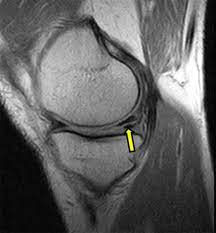

The mri can take between 20 minutes and 1 hour, depending on the body part. We scan axial (top to bottom) sagittal (right to left) and coronal (front to back). A doctor is trained for over 11 years (many specialists are trained even longer) to make the right decisions on behalf of patients. Your mri exam may take as little as 15 minutes or as long as an hour depending on the type and number of exam(s). In this video scott will take you through the procedure of receiving an mri for your knee. Mri results are usually available to a doctor within one to two days, reports webmd. The scan is painless and can take anywhere from 15 to 90 minutes depending upon what the mri is scanning. The mri of the knee will take approximately 30 minutes. After arthroscopy, you'll rest your knee for several days, apply ice, and prop up your leg on pillows. Since there can be long wait times to see orthopedic specialists, it may be smart to get an affordable mri scan to diagnose the problem before spending money on a visit to a specialist. One exam produces many images. The knee mri can take 30 minutes to an hour. An mri test usually takes 30 to 60 minutes but can take as long as 2 hours.